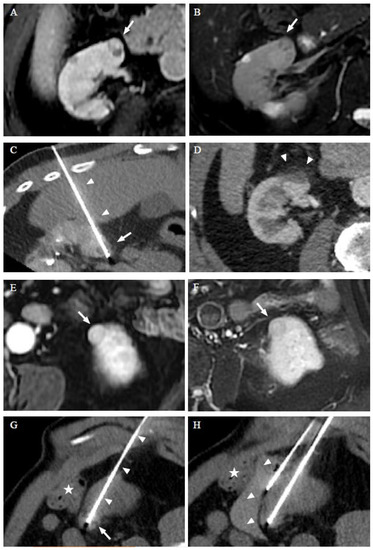

2.2. Procedure

3.3. Thermal Ablation Procedures

3.4. Efficiency and Adverse Effect